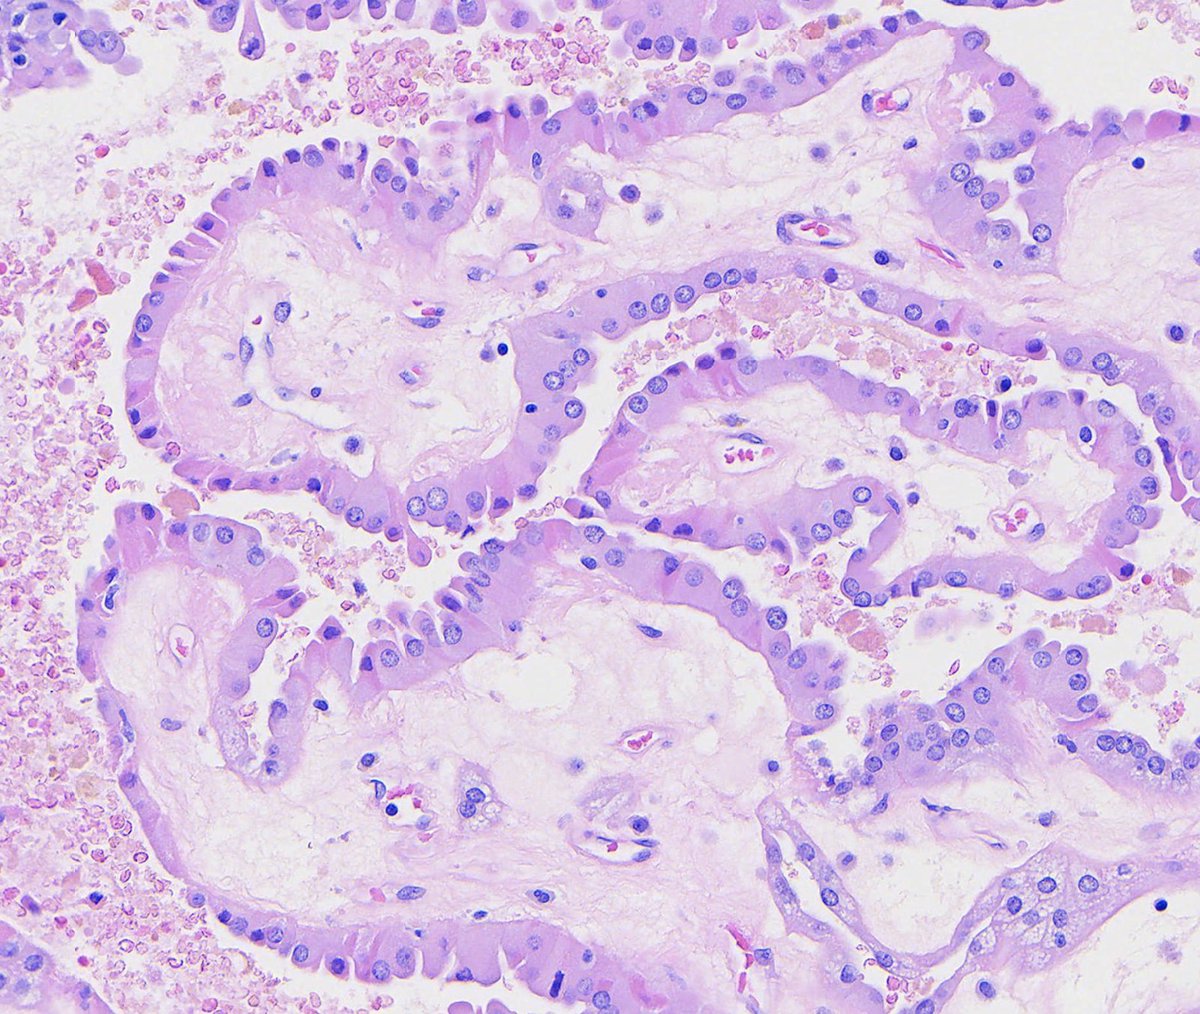

Complete hydatidiform mole: - Single population of large, hydropic villi with irregular "scalloped" borders - Trophoblast proliferation, often in a circumferential pattern around villi See the whole slide and more info: https://t.co/YAOy2uJFM4